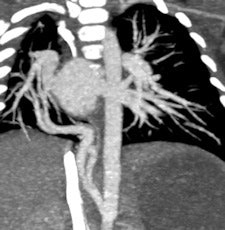

MDCT using a low radiation dose protocol is the best diagnostic tool for assessing the central airway, cardiovascular and mediastinal abnormalities, and the lung parenchyma in children, and the relevant information can be acquired with a single-volumetric data set acquisition, she stated. Using thin-slice collimation acquisition with inherent isotropic resolution, the image data can be manipulated and reformatted to display 2D and 3D images with the same spatial resolution as the axial images, thus enhancing diagnostic accuracy and providing data that can be used in presurgical planning and patient management.